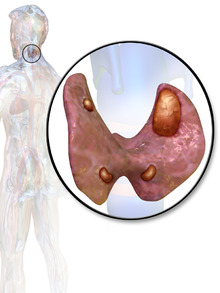

Illu thyroid parathyroid.jpg

Thyroid and parathyroid